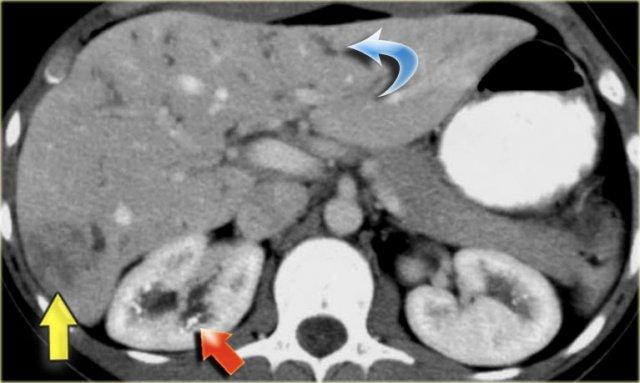

Hãy quan sát hình ảnh bên trái.

Sau đó tiếp tục đọc.

Các dấu hiệu bao gồm:

- Thận xốp tủy kèm hình thành sỏi (mũi tên đỏ)

- Giãn nhẹ ống mật (mũi tên xanh dương)

- Khối giảm tỷ trọng dạng tròn ở thùy gan phải

Khối ở thùy gan phải được xác định là áp xe.

Cần lưu ý rằng áp xe gan trong giai đoạn sớm có thể có hình ảnh khá đặc.

Trong chẩn đoán phân biệt, chúng ta cũng cần xem xét khả năng u tân sinh, vì bệnh nhân mắc bệnh Caroli có nguy cơ tăng cao phát triển ung thư biểu mô đường mật.

Cuối cùng, nếu có xơ hóa đáng kể và toàn bộ gan bị ảnh hưởng, những bệnh nhân này sẽ tiến triển thành xơ gan.

Bệnh nhân bên trái đã tiến triển suy gan nặng và được phẫu thuật cắt gan.

Lưu ý tình trạng giãn ống mật trong gan, lách to và giãn các tĩnh mạch bàng hệ.

Trên bệnh phẩm cắt bỏ có dấu hiệu chấm trung tâm (mũi tên xanh dương) và một ổ mủ nhỏ (mũi tên vàng).